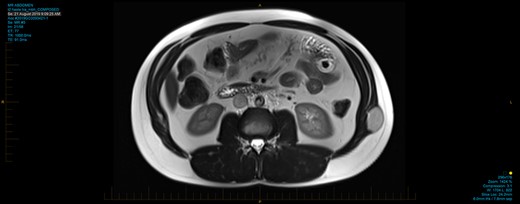

Laboratory studies, including white cell count, haematocrit, electrolytes and liver functions, were all normal. Ultrasound scan of the abdomen showed a 56 × 28 × 27 mm homogenously hyperechoic mass within the muscular abdominal wall with mild internal Doppler vascularity. Provisional diagnosis of fat-containing lumbar hernia was made and a computed tomography (CT) scan of the abdomen was done to confirm the diagnosis. Portal venous phase abdominopelvic CT scan showed an ovoid mass within the external oblique muscle with heterogenous attenuation. There was no calcification, inflammatory changes or evidence of direct invasion into the muscle. Appearances were inconsistent with a simple lipoma and magnetic resonance imaging (MRI) was recommended to rule out sarcoma. The abdominal MRI showed a fairly homogenous mass within external oblique muscle with well-circumscribed borders. The lesion was hypodense to muscle on T1 and hyperdense to muscle on T2 weighted images (Fig. 1). There were avid enhancement and some diffusion restriction suggesting high cellularity. Prominent feeder vessels were present. Differentials of undifferentiated sarcoma, fibroma or desmoid tumour were considered. A core biopsy was performed showing brown fat without evidence of atypia consistent with intramuscular hibernoma.

Axial section of abdominal T2 weighted MRI showing hyperintense mass within the left external oblique muscle.